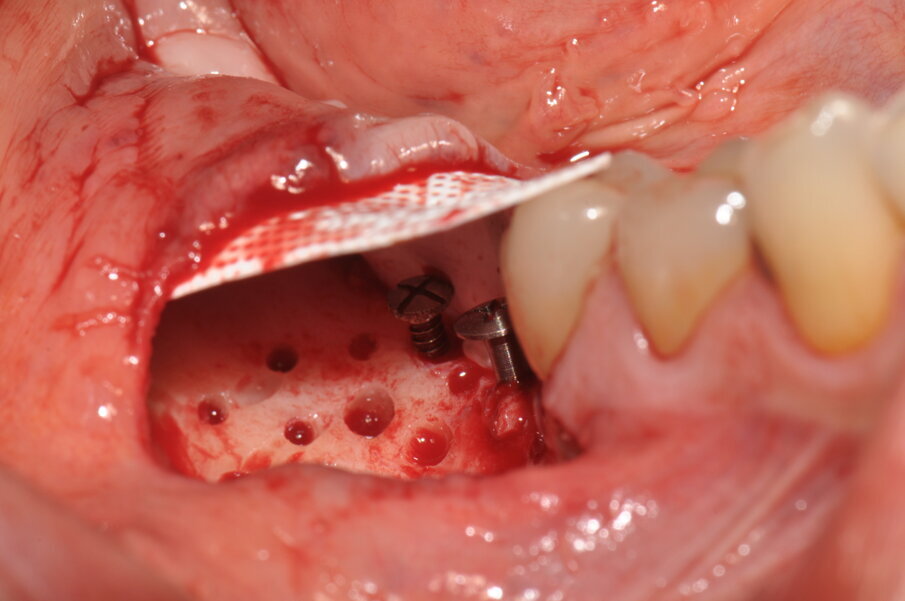

Figg. 5, 6_Si effettua la perforazione del letto osseo ricevente, il fissaggio linguale della membrana Cytoplast tireinforced ed una miscela 1:1 di osso autologo ed eterologo.